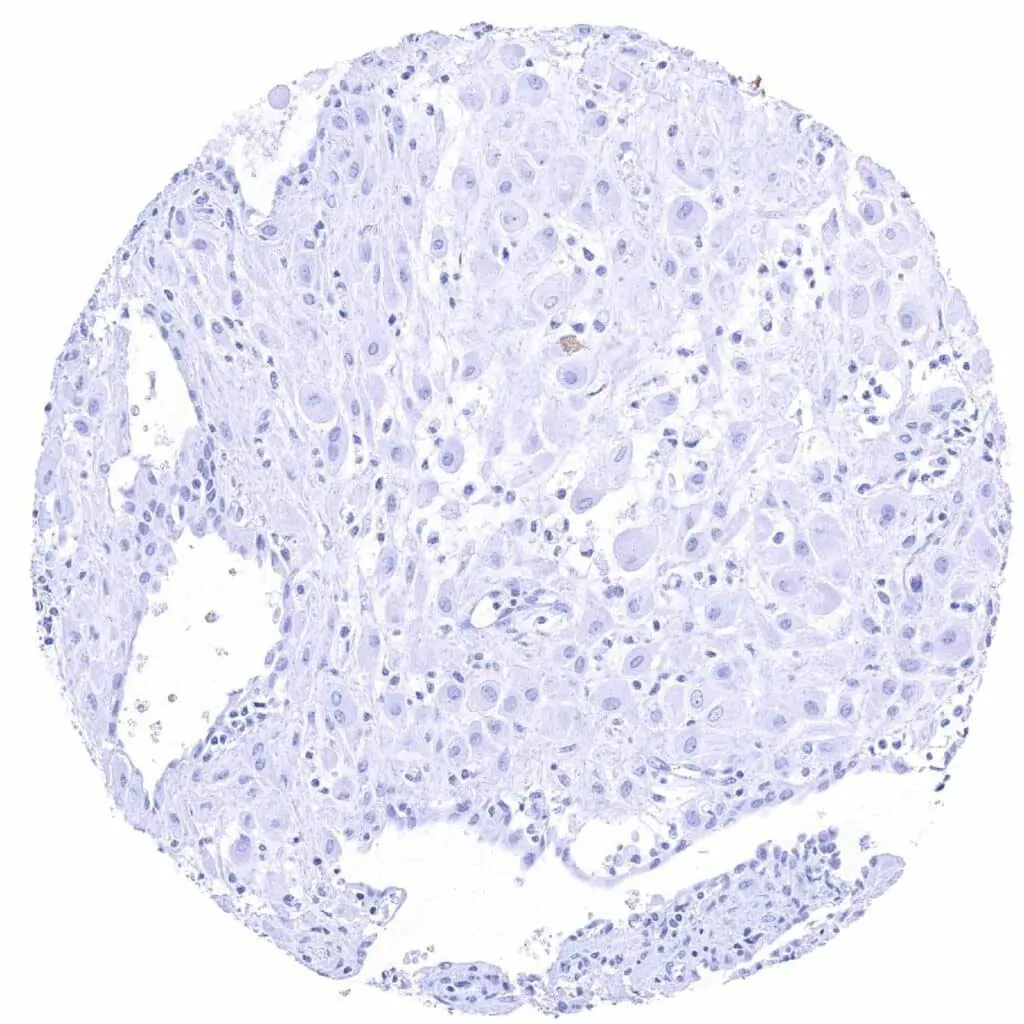

Uterus, ectocervix